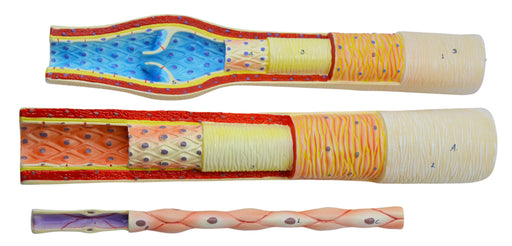

3 Piece Artery, Vein and Capillary Model Set, 13 Inch - Enlarged - Numbered - Cross Sections - Eisco Labs

3 PIECE SET || 3-dimensional model set includes enlarged artery, vein and capillary models showing cross-sections and interior structures FEATURES...